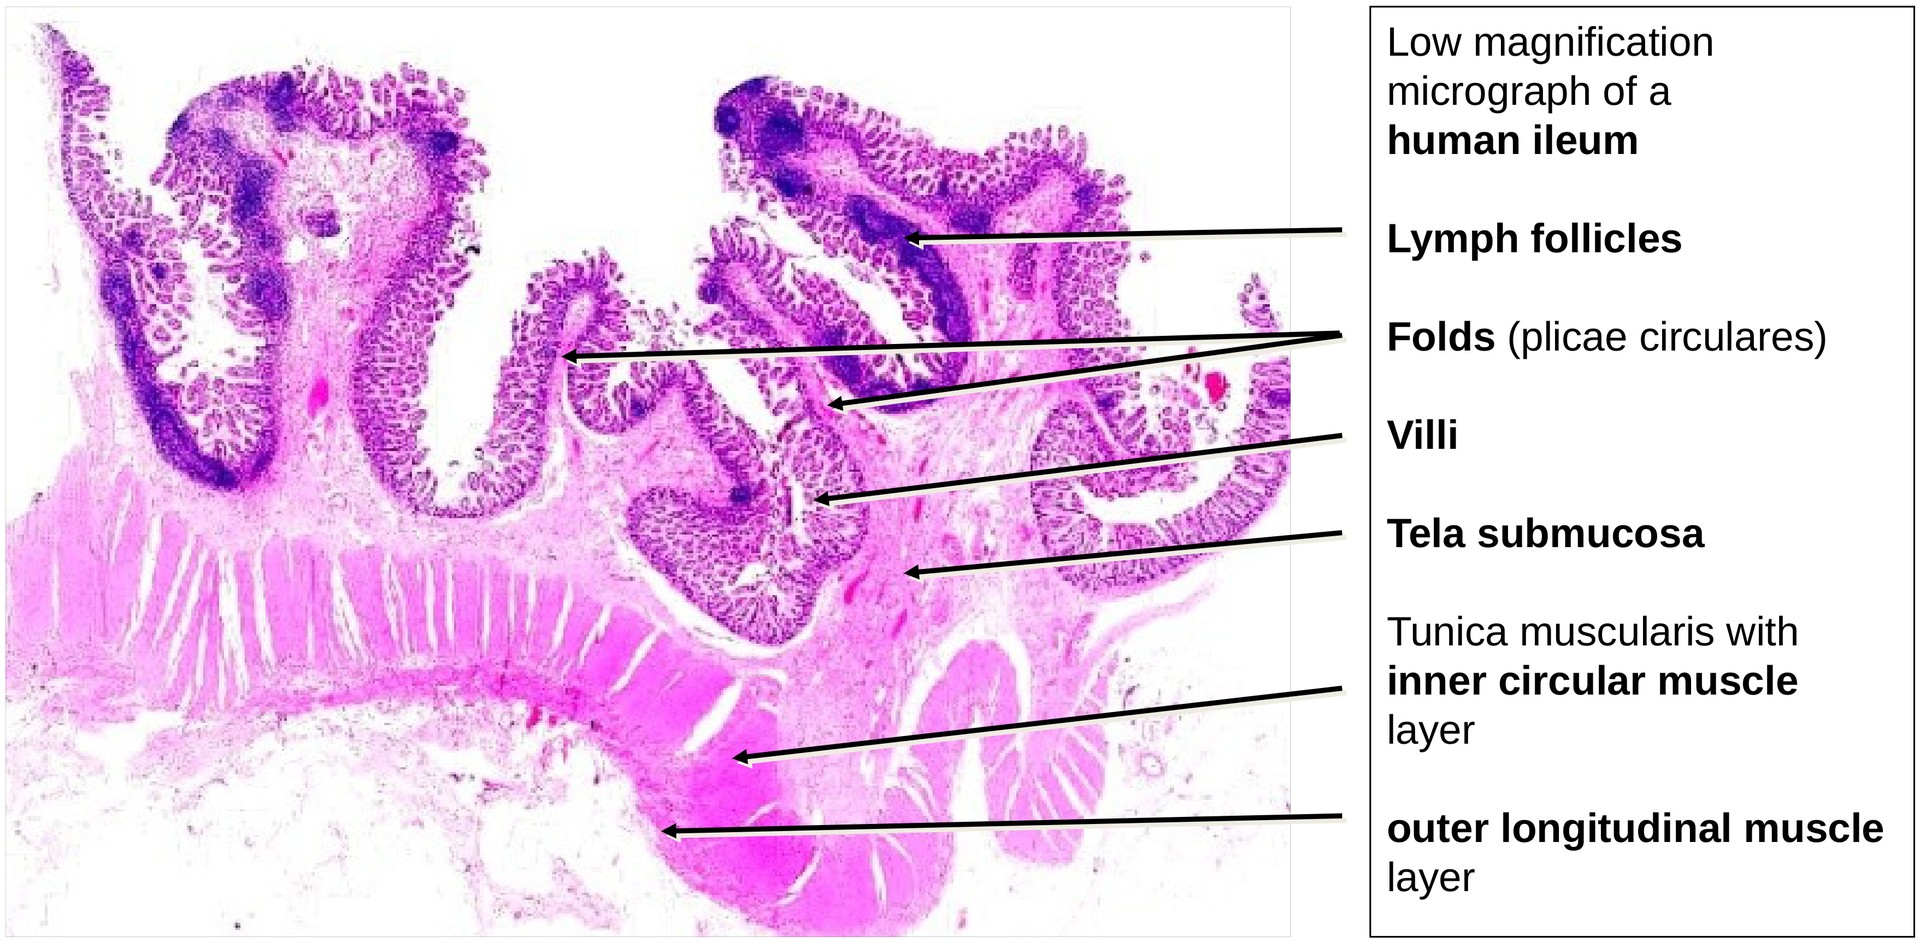

The general layered organization of the GIT wall is well preserved: - Tunica mucosa (with lamina epithelialis, lamina propria, and lamina muscularis mucosae). - The muscularis mucosae is relatively thin but extends into the circular folds and occasionally into the villi. - Tela submucosa, which appears robust but shows few identifiable elements of the submucosal plexus (Meissner’s plexus). - Tunica muscularis, composed of: - An inner circular layer (particularly prominent here). - An outer longitudinal layer, between which the myenteric plexus (Auerbach’s plexus) is clearly visible, containing ganglion cells and nerve fibers.

The circular folds (plicae circulares) are lower than those seen in the duodenum or jejunum. No glands are found in the submucosa (unlike Brunner’s glands in the duodenum).